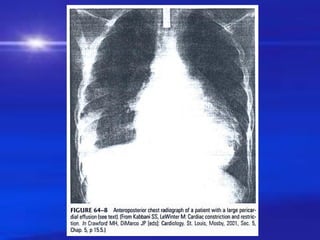

❖ X quang:

– To, Baàu nöôùc hoaëc bình thöôøng hay gaàn bình thöôøng

– Ñöôøng môõ maøng ngoaøi tim

– Soi XQ : Boùng tim ñaäp yeáu

X quang ngöïc

Boùng tim bình thöôøng hoaëc baàu nöôùc

Bieåu loä beänh lyù phoåi / trung thaát theâm vaøo